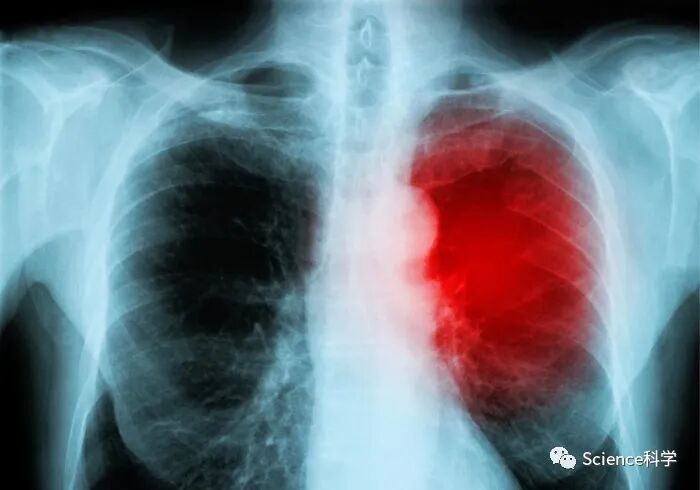

世界卫生组织将最近出现的新SARS-CoV-2变体正式命名为奥密克戎(Omicron),一周多后,全球至少有38个国家和地区发现了这种变体。来自南非的两份新报告提供了一些非常早期的见解,即随着这种新变体的迅速传播,它在人类中可能会有怎样的表现。

南非Tshwane地区(奥密克戎变体爆发的中心)的研究人员提供的一份病人资料表明,与之前的变体相比,新的变体可能导致较轻的疾病。一项再感染研究表明,奥密克戎导致以前感染过该病毒的人出现高比率的SARS-Cov-2病例。

南非医学研究理事会(SAMRC)的一份新报告提供了目前在Tshwane地区医院综合大楼住院的COVID-19患者的情况。该报告由在SAMRC工作的医生Fareed Abdullah撰写,对感染COVID-19奥密克戎变体的住院患者的情况进行了初步了解。

Abdullah谨慎地指出,该报告只是基于在奥密克戎新一波疫情的前两周所见的病人,所以这些病人情况完全有可能在未来几周内发生变化。然而,早期的迹象表明,这波奥密克戎变体引起的疫情与之前在Tshwane本地地区看到的疫情非常不同。

本分析报告的主要观察结果是,COVID-19病房中的大多数病人都不依赖氧气。目前很少有病人需要补充氧气,Abdullah报告说,这与之前一波COVID-19疫情中的医院情况明显不同。有趣的是,这些病人中的大多数最初是由于其他医疗原因被送入医院的,而常规检测发现了SARS-CoV-2感染。

报告指出:“这是在前几波中没有看到的情况,在前三波的开始和整个过程中,COVID病房中总是只有零星的病房病人,这些病人通常处于恢复阶段,等待出院前的合并症的好转。COVID病房可以通过大多数病人使用某种形式的氧气补充,以及高流量鼻氧机不间断的声音或呼吸机的警报声来识别。”

使这些有希望的迹象复杂化的事实是,Tshwane的大多数COVID-19住院患者都是年轻人。事实上,根据SAMRC的报告,在过去两周里,80%的COVID-19住院病人是50岁以下的人。

Abdullah推测,年轻人中较高的阳性病例率可能是疫苗对奥密克戎起作用的一个迹象。他指出,当地50岁以上的人中有57%接种了疫苗,而50岁以下的人的接种率只有34%。